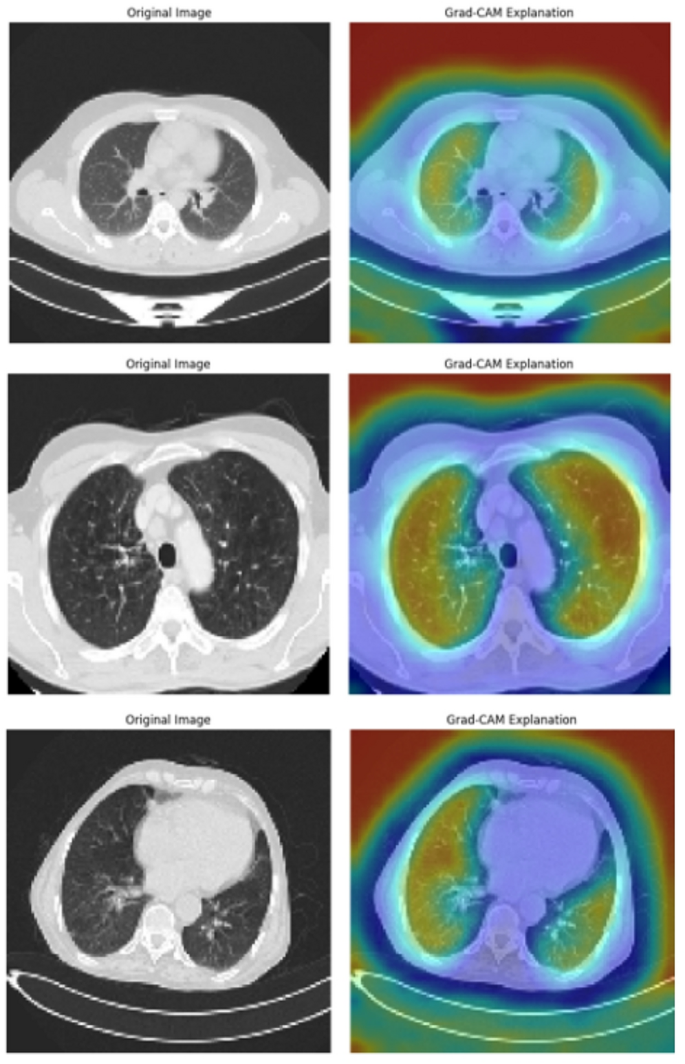

Grad-CAM heatmaps highlighting key regions contributing to lung cancer predictions.

Figure 16 presents the Grad-CAM visualizations applied to the global model for lung cancer detection. The left column shows the original CT scan images, while the right column highlights the regions of interest using heatmaps. Warmer regions (red, yellow) indicate areas where the model focused on decision-making, whereas cooler regions (blue, green) reflect less significant areas. These visualizations, along with the broader XAI-based analysis employed in this study, provide an interpretable explanation of the model’s predictions. Specifically, we utilized Local Interpretable Model-agnostic Explanations (LIME) and Grad-CAM to identify and highlight the most influential features contributing to the model’s decisions. LIME perturbs the input data to build a simple local model that approximates the global model’s behavior, identifying key superpixels affecting the output. At the same time, Grad-CAM uses gradients to generate heatmaps that localize important areas in the image. These techniques help clinicians verify that the AI is focusing on medically relevant lung regions—such as nodules or tumors—rather than irrelevant artifacts, thereby enhancing trust, transparency, and acceptance of the system in clinical settings.